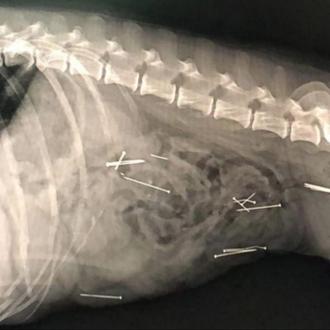

Una perra de 13 años se está recuperando favorablemente tras haberse comido algún tipo de …